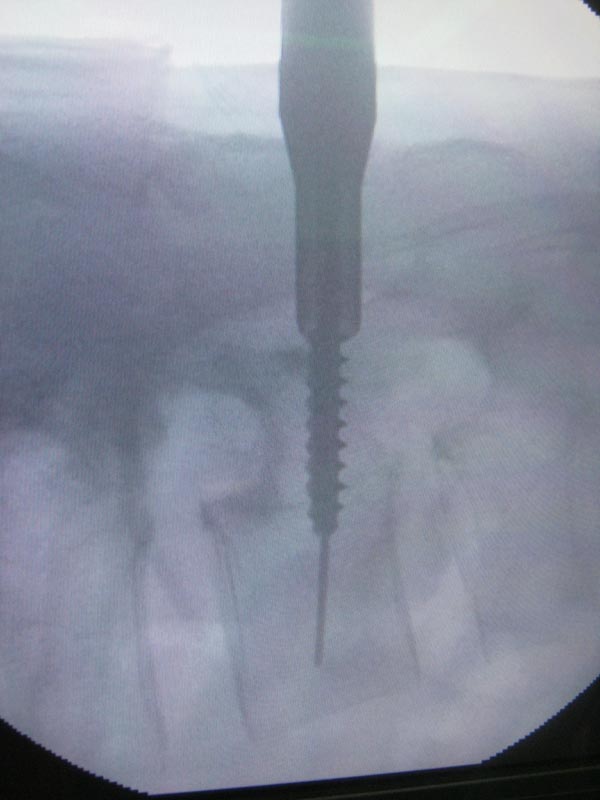

术中经皮置钉的透视情况